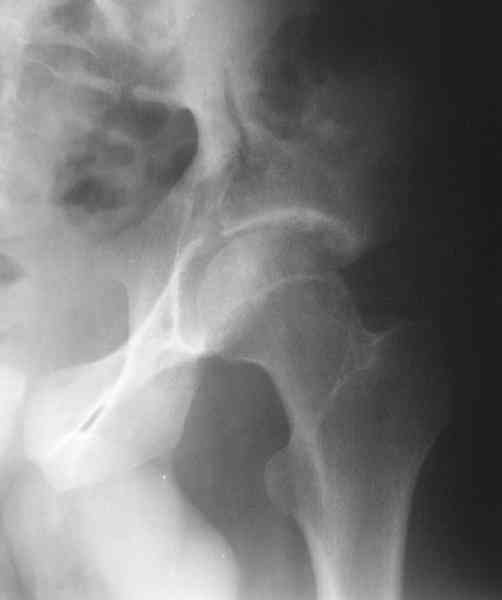

What is your indication for surgical management? What kind of fracture do you think it is? It looks like a transverse type although it has been a couple of years since I looked at an acetabular fracture.

The last two images from the 3-D CT scan certainly makes the fracture look worse than the plan radiographs.

The joint is non-concentric as the head appears to be either "following the caudal segment", or the dome component is displaced from the tethered head... or so it seems... and he's young... so, many fracture surgeons would recommend reduction and fixation.

Some more images. Does it help to guess which part of the acetabulum is displaced?